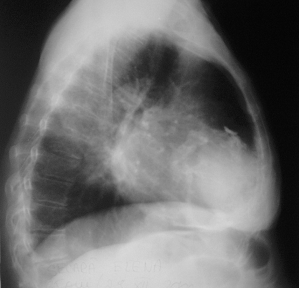

Imagine Rx de pericardita acuta

Semne radiologice cardiopulmonare:

cardiomegalie importanta cu contururi net trasate, stergerea arcuatiei normale, cord 'in carafa',

circulatie pulmonara normala.